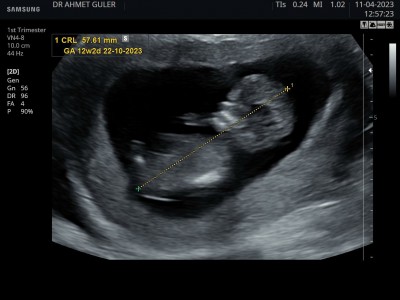

12+2 biliyorum  cinsiyet için  çok erken ama  merak işte  ilk çocuğum oğlan sizce kafa yapısına göre cinsiyeti nedir bilginiz var midir.

Gebelik haftası 12